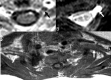

A, In a patient with a history of breast cancer surgery and radiation treatment with right-arm weakness, axial T2WI shows diffuse thickening of the right PBL with no associated hyperintensity (arrow). B and C, Pre- (B) and postcontrast (C) axial T1WIs show minimal contrast enhancement of the thickened right BPL fibers with no associated nodularity (arrows). Findings are suggestive of radiation fibrosis rather than metastasis.

Fig 10.